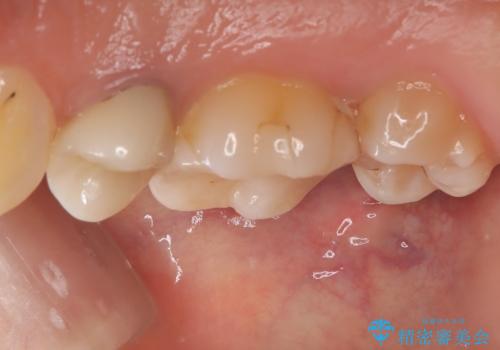

- 元々入っていたセラミックインレーは、6番目と7番目の歯の隙間を無理やり咬合面の近遠心的幅径を伸ばし埋めたような形態で、下部鼓形空隙が広めで食渣が溜まりやすい状態でした。

セラミックインレーを除去したところ、残存歯質が少なく破折のリスクを説明し、オールセラミッククラウン(スタンダード)でのやり替えとなりました。